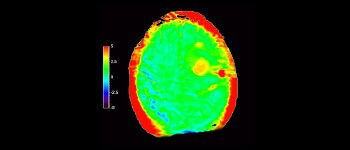

In una società in cui i disturbi neurologici rappresentano un grave problema, Philips si impegna a fornire una efficacia diagnostica senza pari e una guida per il trattamento di tutti i pazienti. Oggi, sebbene la risonanza magnetica sia lo standard di riferimento per l'imaging neuro-oncologico, è comunque possibile migliorarne la precisione nella definizione del grado del tumore e nelle valutazioni di follow-up della terapia. 3D APT (Amide Proton Transfer) è un esclusivo metodo di imaging RM del cervello senza contrasto che permette di ottenere diagnosi più affidabili nel campo della neuro-oncologia. Si avvale della presenza di proteine cellulari endogene per produrre un segnale RM direttamente correlato alla proliferazione delle cellule, un marker dell'attività tumorale. 3D APT è un valido supporto per il personale medico specializzato nella distinzione dei gliomi di grado basso e alto, e nella differenziazione della progressione del tumore rispetto agli effetti della terapia1.

A circa 70 esami RM di bambini affetti da tumore al cervello sono state aggiunte immagini APT e abbiamo osservato precocemente risultati incoraggianti”